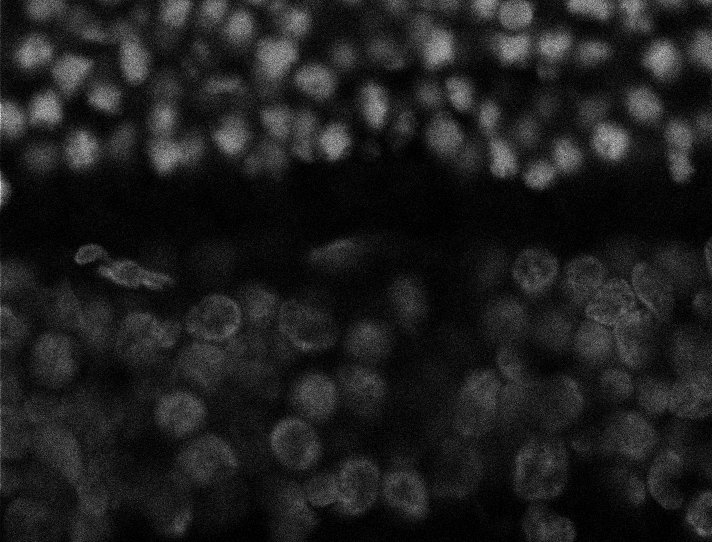

Nuclei

Nuclei - Bip